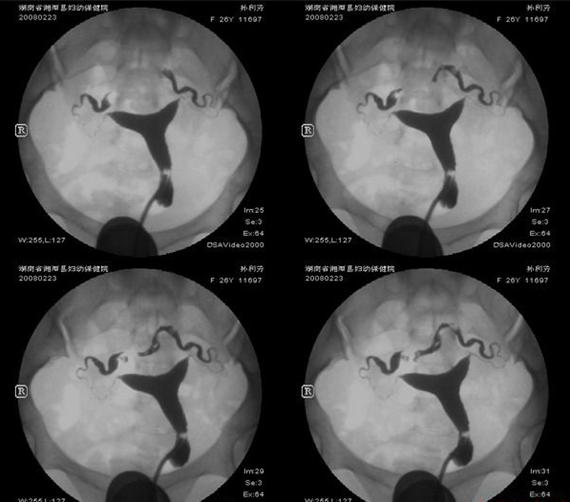

她輸卵管阻塞,做了3次試管嬰兒都失敗,轉到博元婦產科,先以腹腔鏡手術,再做試管嬰兒,竟3胞胎 不孕症: 雙邊輸卵管阻塞 ...